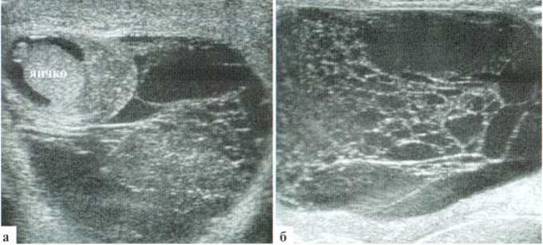

Рис. 2.1.2. Крупные размеры трансформированной гидатиды: 1 — яичко, 2 — гидатида. Размеры яичка и гидатиды практически одинаковы. Сосудистый рисунок при ДДС в гидатиде не прослеживается (б)

У детей раннего возраста изменения придатка бывают выражены еще более резко, по размерам он может приближаться к размерам яичка, форма его чаще становится неправильной. Всегда имеет место резкое усиление сосудистого рисунка (рис. 2.2.3).

Рис. 2.2.3. Эпидидимиту младенца. Придаток (2) по размерам практически одинаковый с яичком (I), резко гиперемирован

В некоторых случаях контуры придатка бывают нечеткими, а структура — мозаичной, с чередованием участков повышения и понижения эхогенности (рис. 2.2.4). Динамическое УЗИ позволяет оценивать регресс воспалительных изменений придатка, при этом он постепенно (5—15 суток) уменьшается в размерах, нормализуется его структура, исчезает гиперемия.

Рис. 2.2.4. Эхографический вариант эпидидимита у новорожденного. Придаток (2) имеет резко неоднородную структуру, по размерам крупнее яичка (1). При ДДС (6) определяется выраженное усиление сосудистого рисунка в придатке